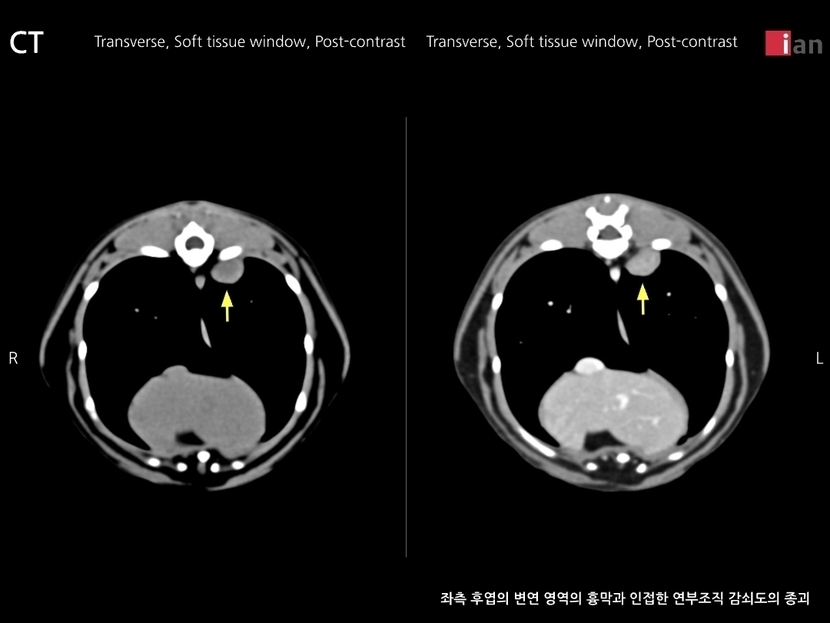

코오는 폐에 종양이 발견되었어요.

내일 수술인데 좀 무서워요.